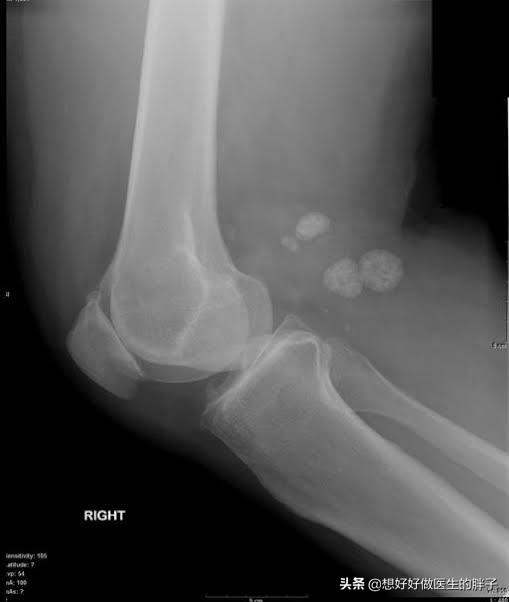

常见的导致关节内存在游离体的病因,多数是由于关节受到外伤以后,关节腔的软骨脱落到了关节腔内,有的时候这些脱落的软骨会慢慢的被磨损吸收掉,而有的时候这些软骨会慢慢变成钙化形成游离体。(下图就是软骨破裂的影像学资料)

另外还有一种比较常见的情况是关节腔的滑膜软骨瘤病,这种情况就类似于患者的关节腔内滑膜变成了一个巢穴,从巢穴内不停地往关节腔内生产软骨样的游离体。(下图为滑膜软骨瘤病的影像学资料)

由于这些游离体在关节腔内,会发生位置的变化,所以也被称之为关节鼠,有的时候这些游离体会卡别在关节腔内,造成患者出现打软腿的症状,如果卡别的比较急骤的时候,患者就会出现明显的疼痛。

一般情况下,关节腔内游离体的诊断,进行膝关节x线检查就可以明确了。(下图在膝关节后方的都是游离体)